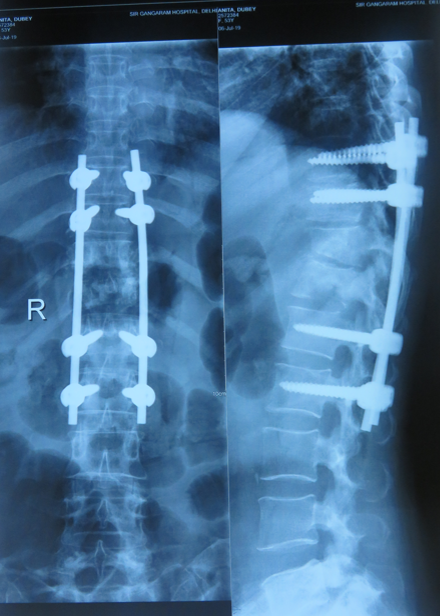

He received his spine training from the renowned Sir Ganga Ram Hospital, New Delhi — catering to over 1500 spinal surgery patients every year — and was awarded the degree of FNB (Fellowship National Board, Spine Surgery). FNB Spine Surgery is the only NMC-accredited fellowship of Spine Surgery in the country.

Our team treats patients who need repair of spinal deformities due to scoliosis, kyphosis, spondylolisthesis, infection, tumors, and trauma — following international standards of care.